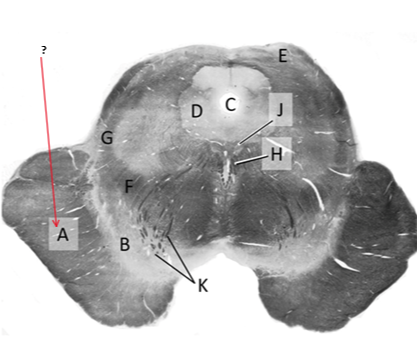

Name this and state its function.

Tectum.

Name this and its divisions+ function?

Substantia nigra.

Cerebral aqueduct.

Crus cerebri.

Medial Lemniscus.

Name this, what is it and state its function.

Lateral lemniscus.

Name this, state its function[2 marks] and how it goes about its function[4 marks].

Medial longitudinal lemniscus.

How?

Oculomotor nucleus.

Name this, state its function[3 marks] and cells involved contributing to function.

Periaqueductal grey.

Root fibres of Oculomotor nerves(CN III).